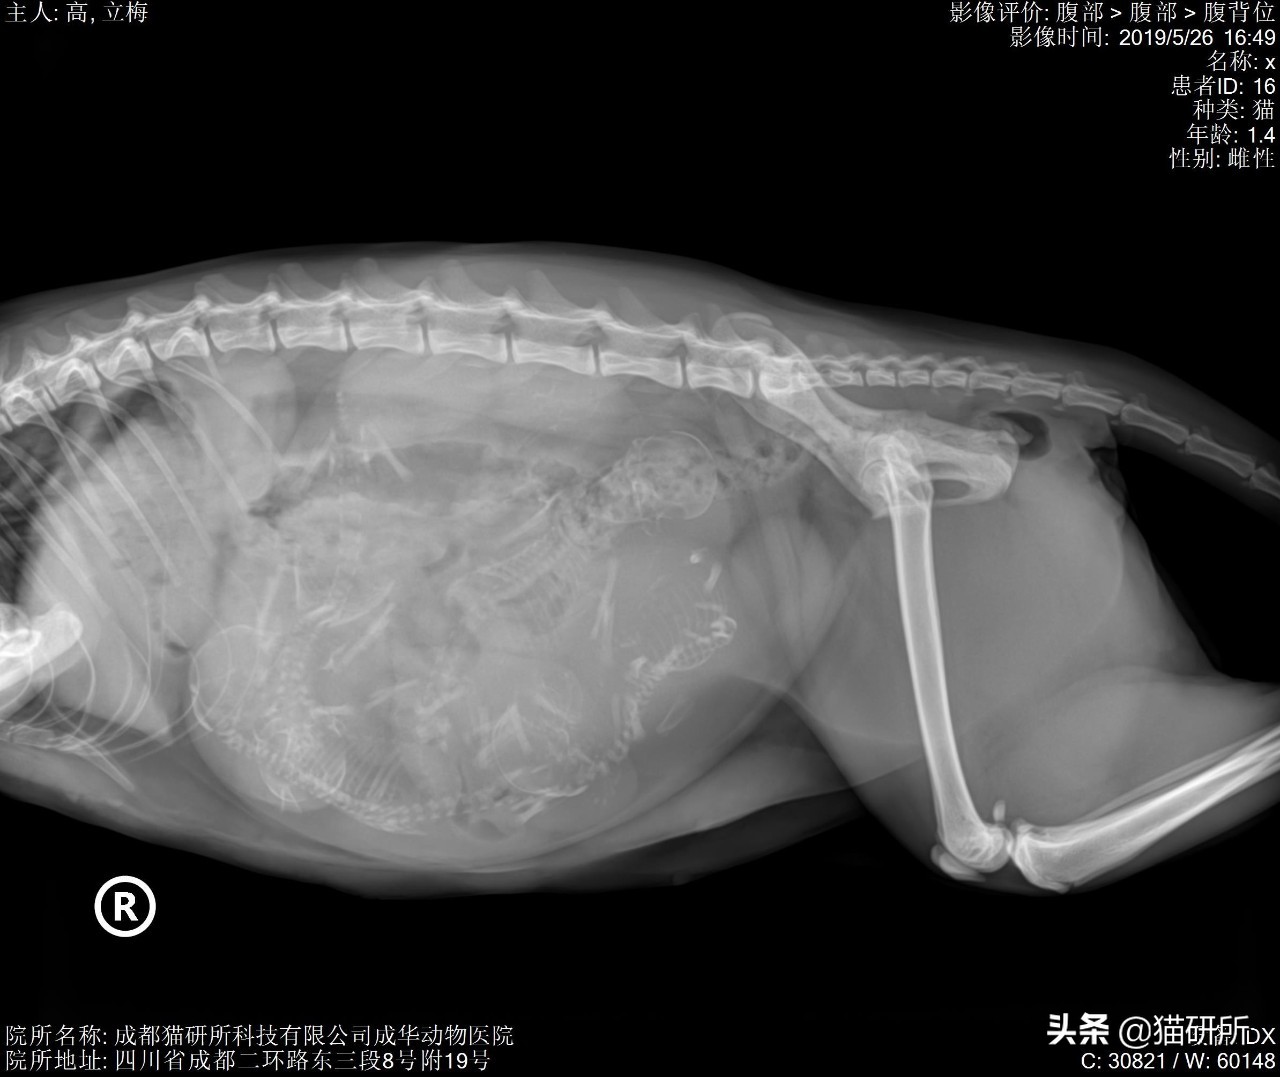

最后,大家一起来猜猜看这只猫咪吃了多少条鱼吧?

图自:猫研所动物医院